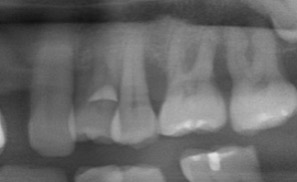

微創牙周再生-陳珮儀醫師

牙齒周邊因為破壞所喪失的骨頭,放置牙周再生材料,重建喪失的牙周

治療後